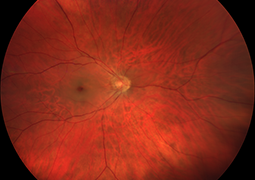

- Choroidální neovaskulární membrána u dětí, dlouhodobé výsledky terapie anti-VEGF preparátem

- Postradiačná makulopatia u pacientov s malígnym melanómom corpus ciliare a chorioidey po stereotaktickej rádiochirurgii